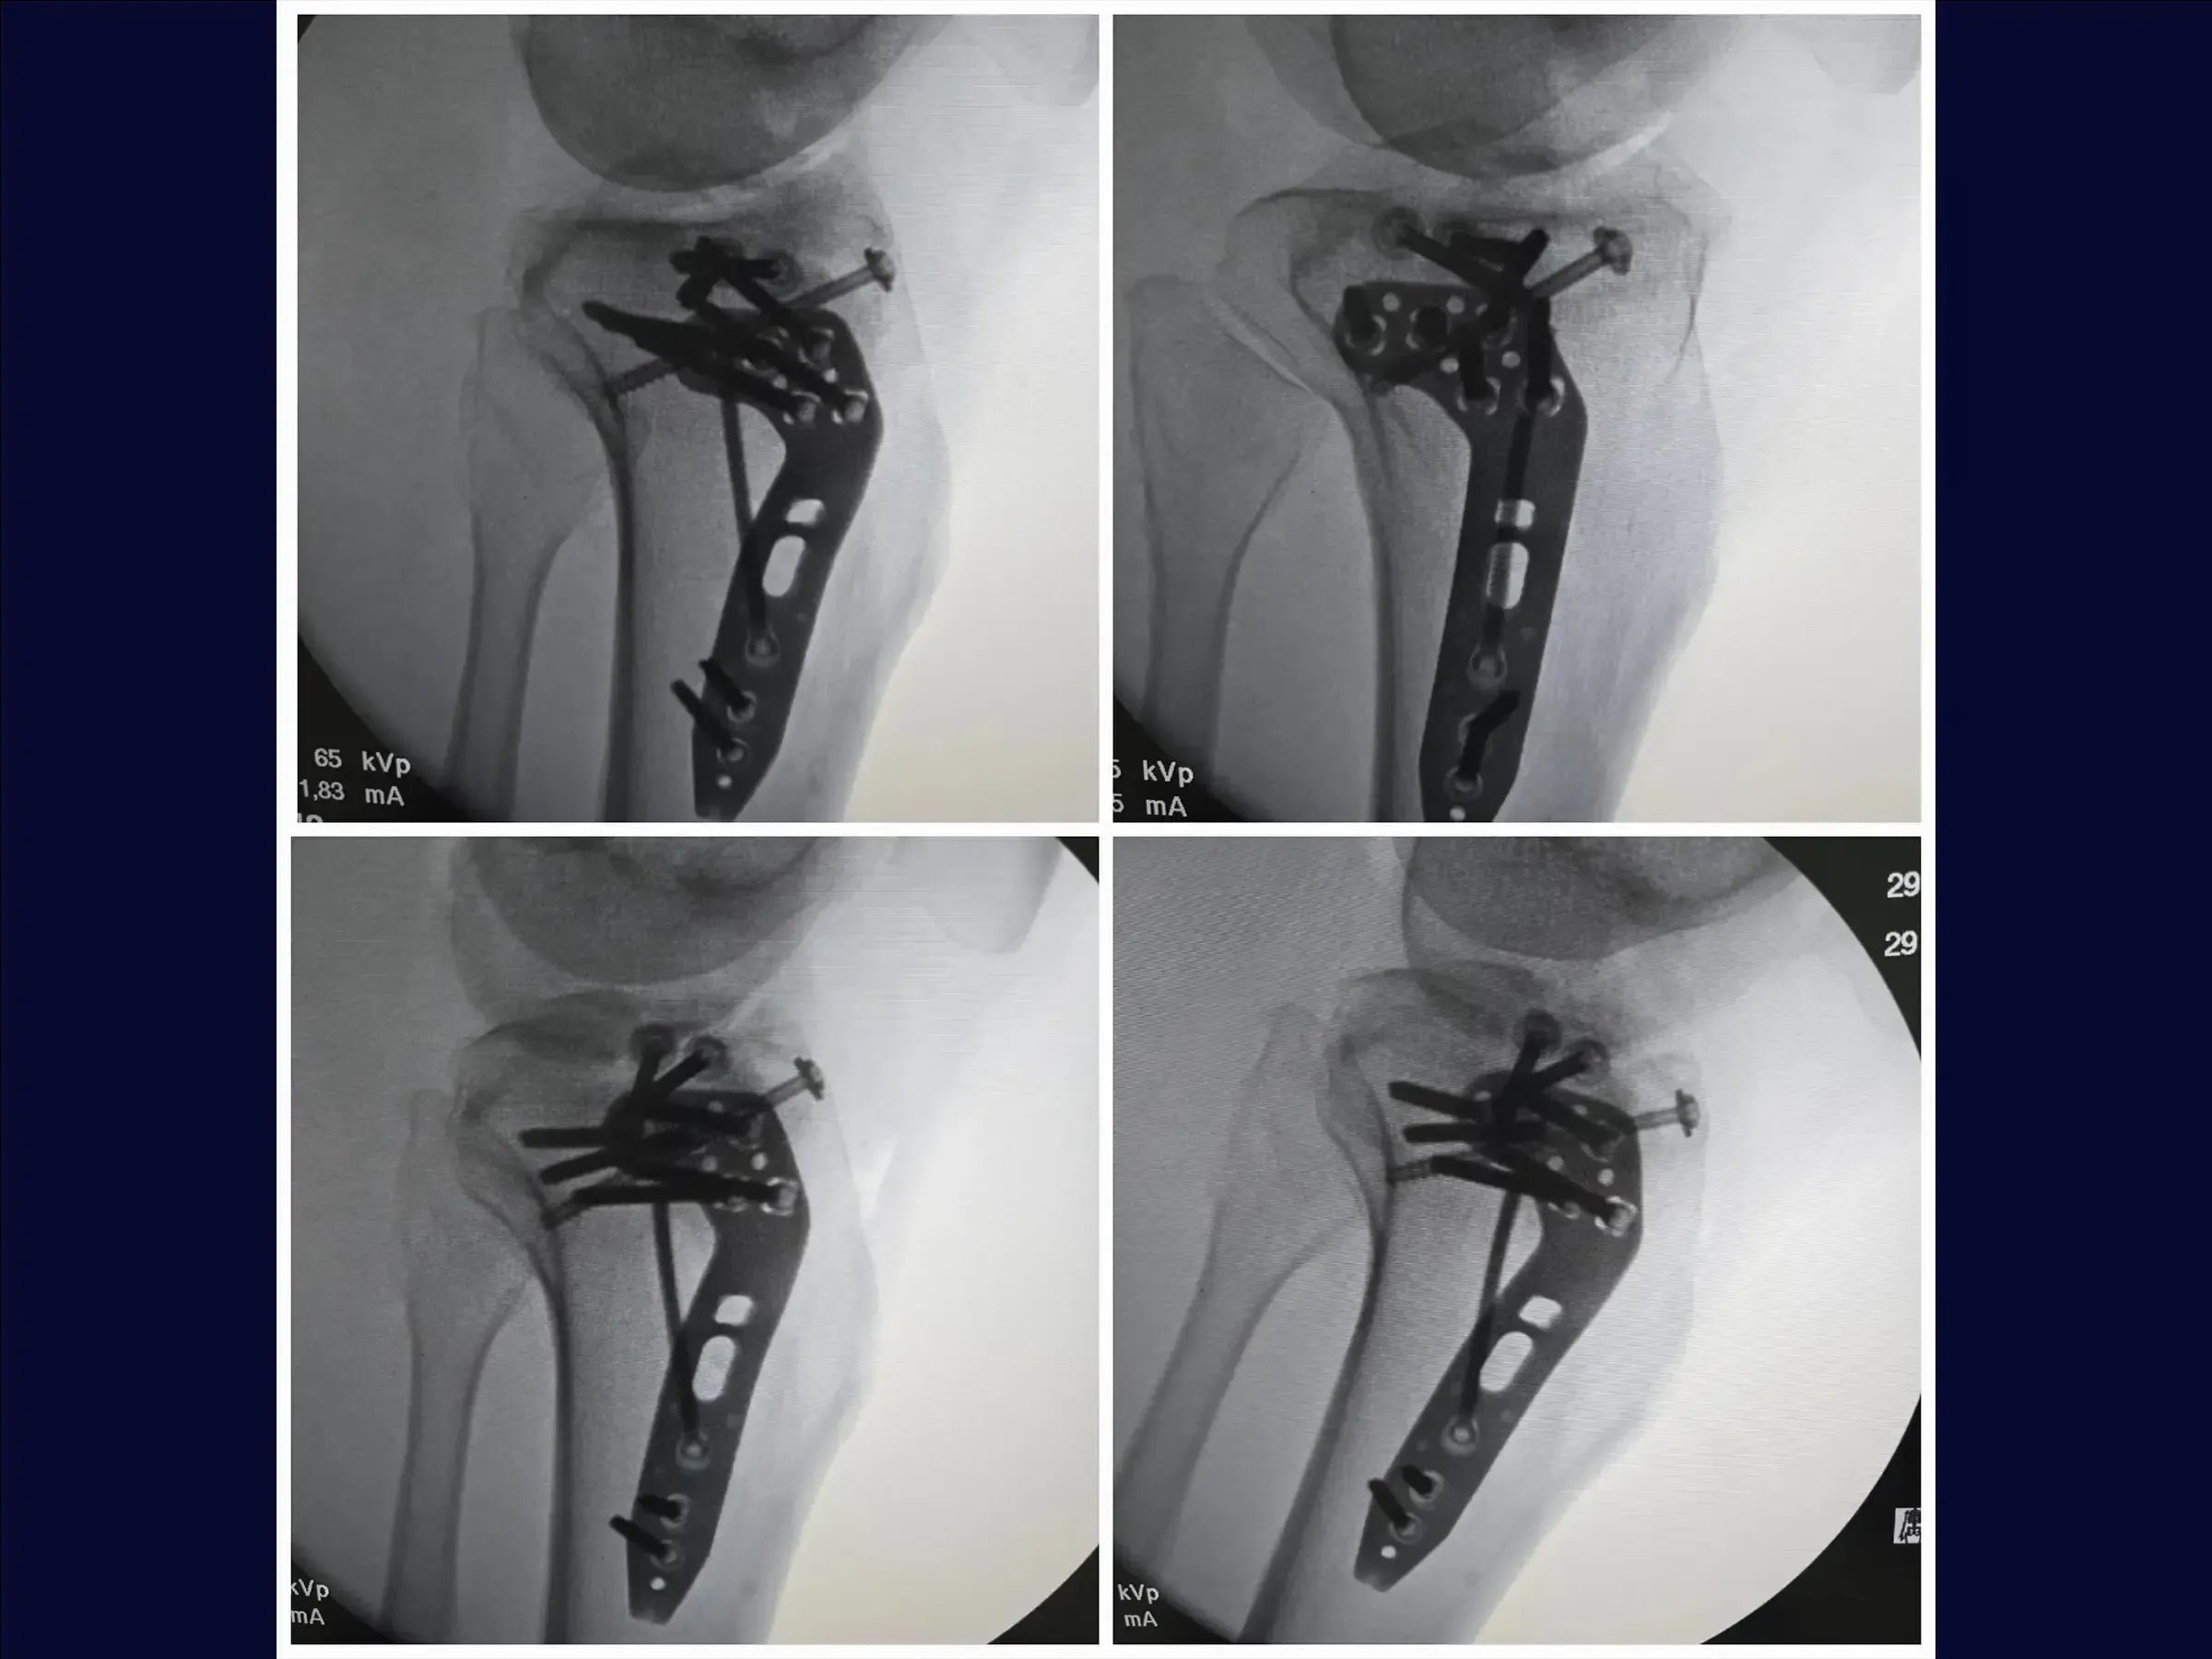

- Utilização de enxerto ósseo estrutural e fixação com parafusos canulados subcondrais e placa.

- Fixação Estável e Rede Subcondral: Posicionamento de fios guia para parafusos canulados subcondrais, criando uma "rede" para estabilidade primária, e utilização estratégica da placa para compressão e manutenção do levantamento.

- Fechamento por Planos para Reestruturação: Abordagem sistemática para o fechamento de tecidos moles e ósseos, reestruturando a anatomia e otimizando o resultado funcional e estético.

- PDF Detalhado: Resumo prático do procedimento, abordando: condição da fratura (platô tibial com afundamento central e cisalhamento incompleto); acesso cirúrgico anterolateral em "taco de hóquei"; preparação e dissecção detalhada; manuseio do menisco e osteotomia incompleta (elástica); levantamento da depressão e enxertia; fixação com parafusos canulados e placa; e fechamento por planos para restauração anatômica e tecidual, culminando em redução anatômica e boa estabilização.